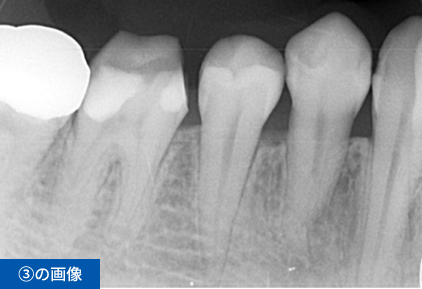

右下6番目の歯が、冷たいものがしみて痛いという主訴でご来院されました。